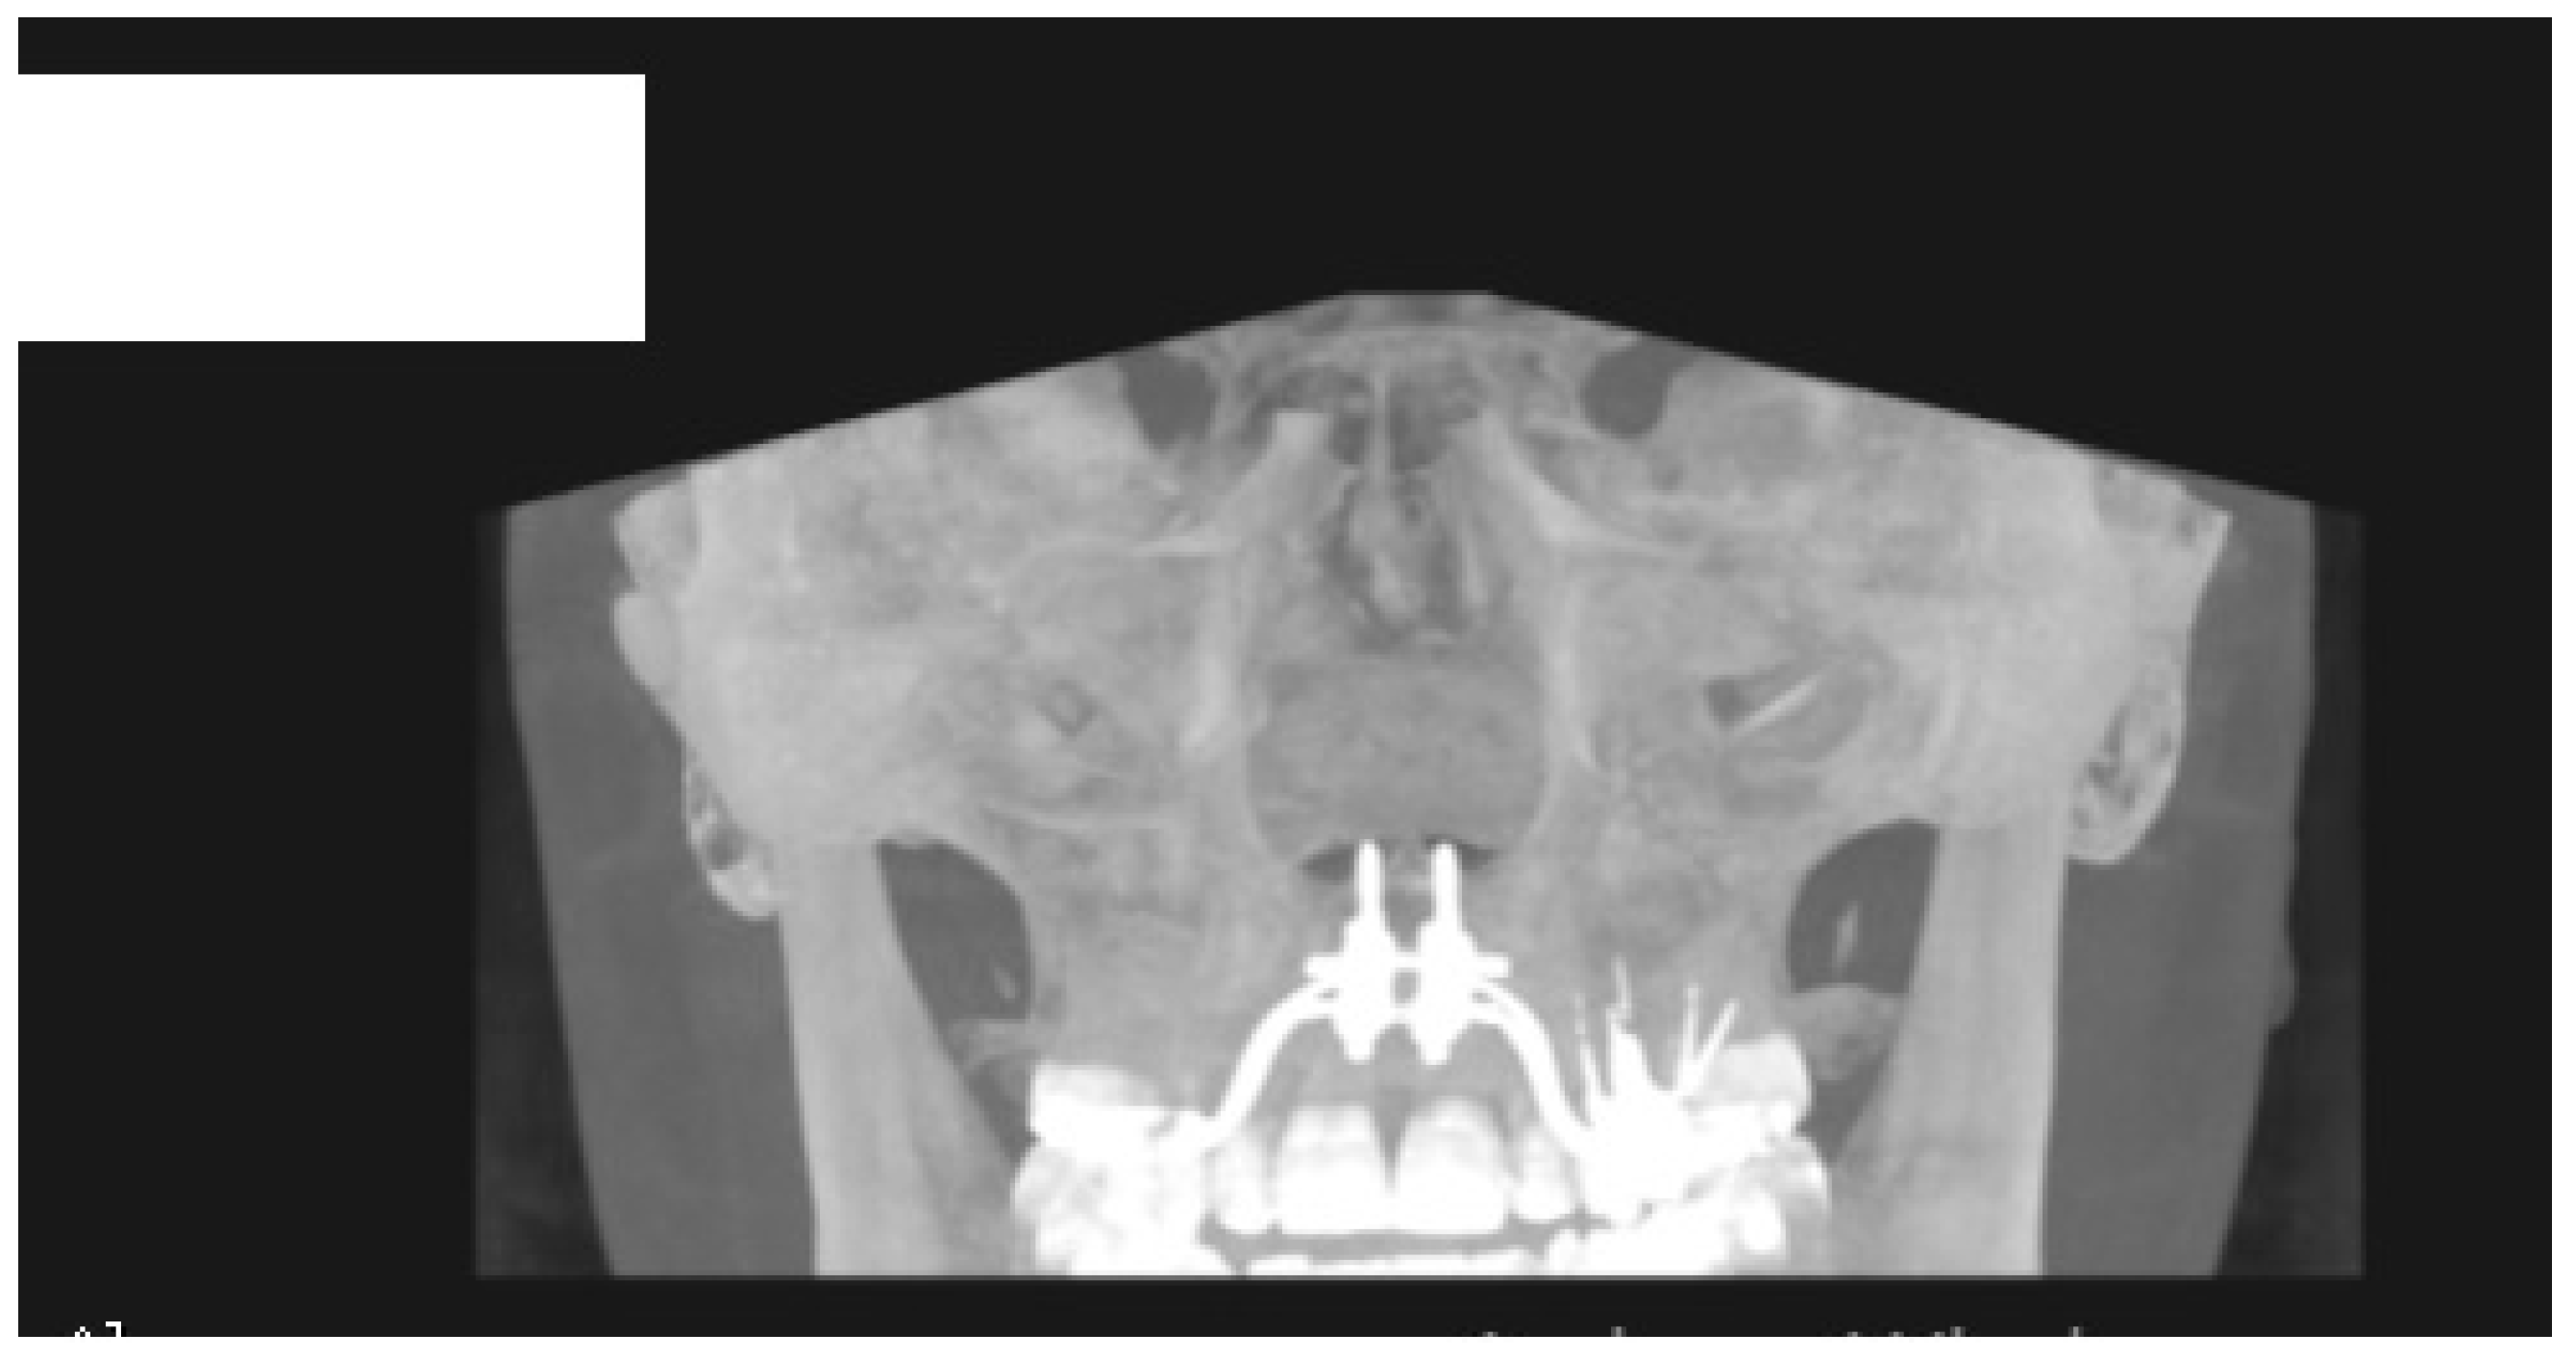

- MARPE associated with cortico-puncture therapy efficiently split the midpalatal suture in adults. The mean split at the anterior nasal spine (ANS) and posterior nasal spine (PNS) was 3.76 and 3.12 mm, respectively. The magnitude of the split at the PNS was smaller than at the ANS (by approximately 85% of the distance), showing that the opening of the midpalatal suture was almost parallel in the anteroposterior direction.

- MARPE therapy associated with cortico-puncture therapy had a positive outcome on midpalatal suture opening and maxillary advancement, but a medium molar inclination of 2.005° was also observed, suggesting that tooth movement cannot be avoided because of the anchorage of the MARPE device at the molar level.